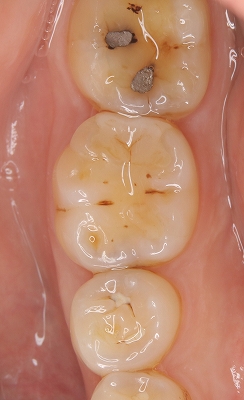

レントゲン

2026 EEdental NNS (1).jpg

口腔内写真

2026 EEdental NNS (2).jpg

低目にレジンが詰めてあります。

患者さんには咬頭が無くなっており、中で虫歯もひろがっていそうだから

メタルアンレーで治しましょうと説明

術前⇒術後

2026 EEdental NNS (5).jpg

2026 EEdental NNS (4).jpg